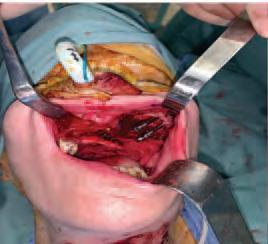

The zygomatic implant perforated (ZIP) flap for rehabilitation of patients with midfacial oncology defects: a report of three cases B. Martin, E. Cotter, C. Bowe, J.E. O’Connell

Issuu converts static files into: digital portfolios, online yearbooks, online catalogs, digital photo albums and more. Sign up and create your flipbook.